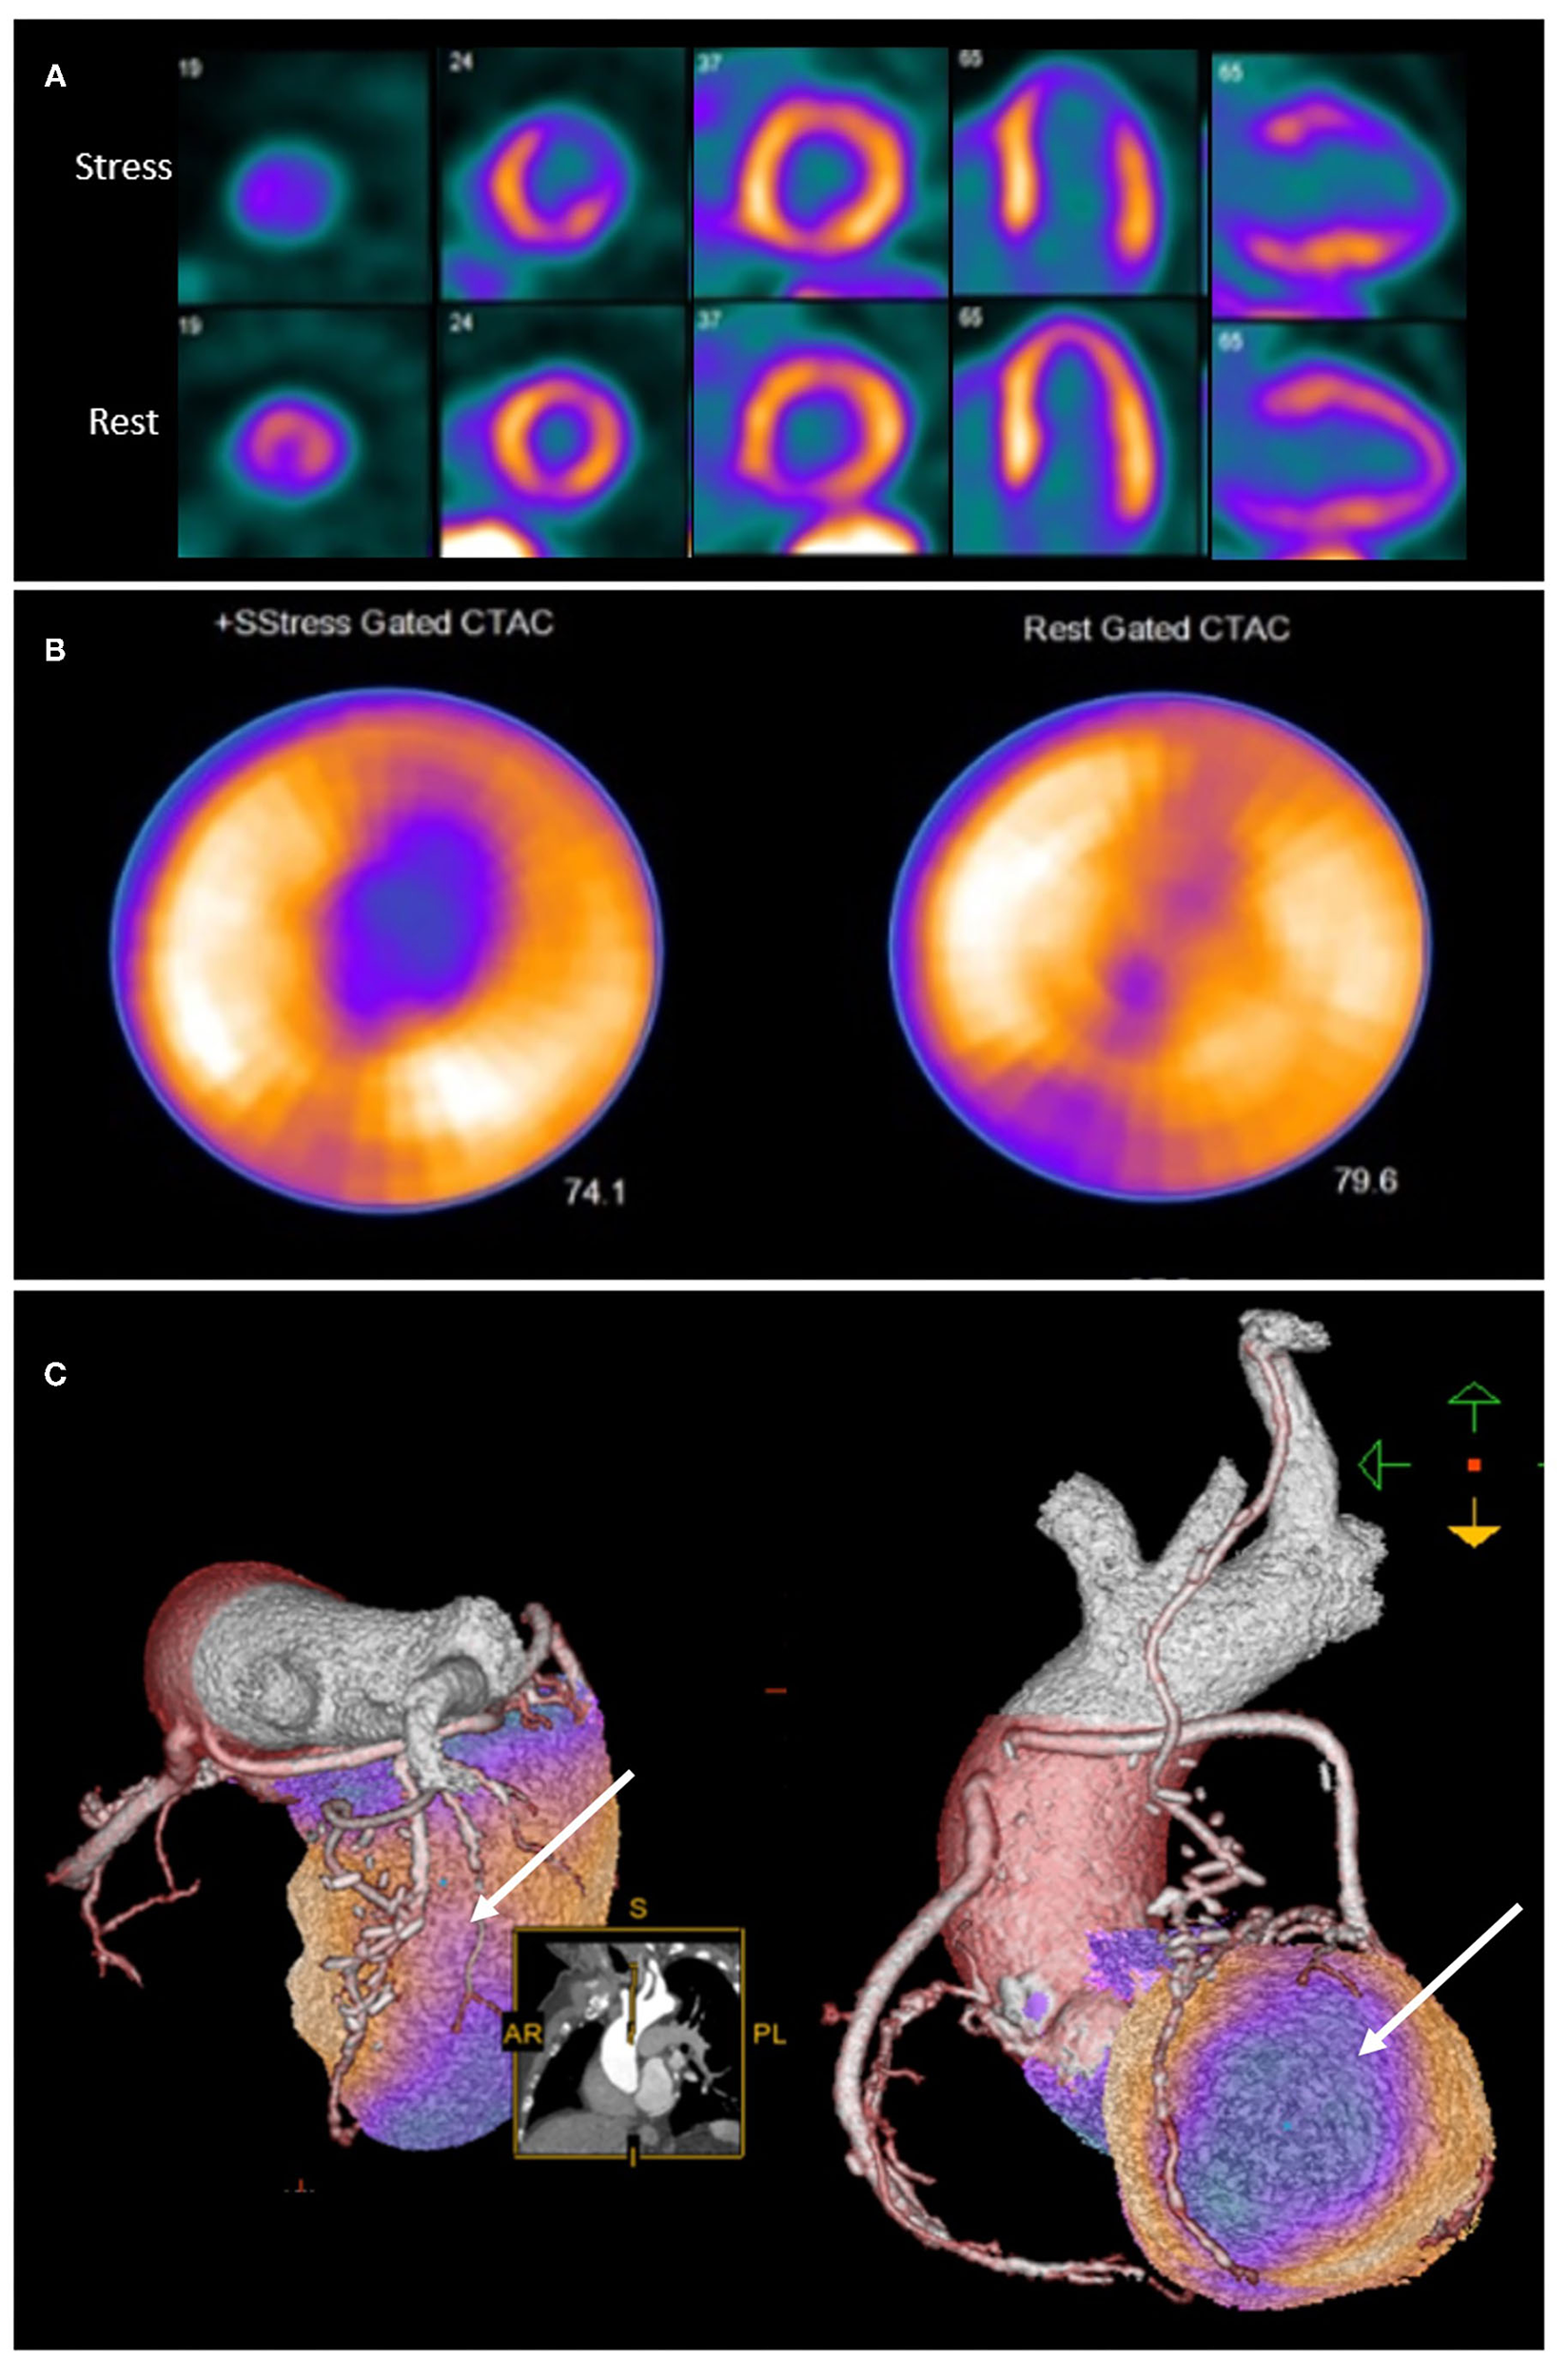

Integration of anatomical and perfusion data may therefore facilitate re-assignment of ischaemia to culprit vessel, and may provide additional insights into the mechanism of ischaemia (43). It is therefore unsurprising that hybrid imaging techniques that combine anatomical and functional testing in patients post CABG provide incremental information on the localization of atherosclerotic lesions (43) as well as prognosis (44) (Figure 2).

Figure 2. Rubidium-82 PET-CT with adenosine stress in an 86-year-old male with previous coronary artery bypass grafting. PET-CT images (A,B) obtained at stress and rest demonstrate a reversible perfusion defect in the mid to apical anterior segments extending into the apex. Cardiac hybrid imaging with three-dimensional fusion of PET-CT with CT coronary angiography enables localization of ischaemia to a coronary artery territory (C). CT coronary angiography reveals a patent LIMA to LAD graft with good distal opacification, and obstructive plaques in the proximal and mid segments of an intermediate artery (white arrow), responsible for the reversible perfusion defect demonstrated.